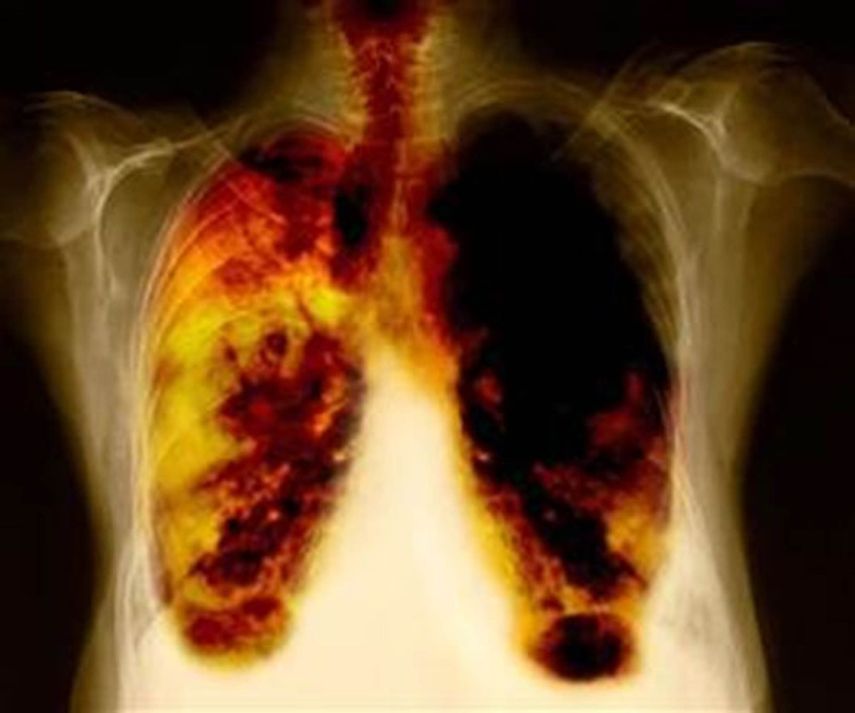

Cáncer de pulmón: Silencioso enemigo

Esta enfermedad, asintomática en su fase inicial, afecta a más de 200 mil estadounidenses cada año

Como enfermedad, el cáncer de pulmón se determina por el crecimiento de células malignas en el tracto respiratorio, específicamente en el tejido pulmonar, y se le clasifica en dos categorías: tumores de células no-pequeñas y de células pequeñas, también llamadas u201cde avena u201d. Esta distinción condiciona el tratamiento, pues mientras el primero requiere cirugía, el segundo es tratado con quimioterapia y radiación.